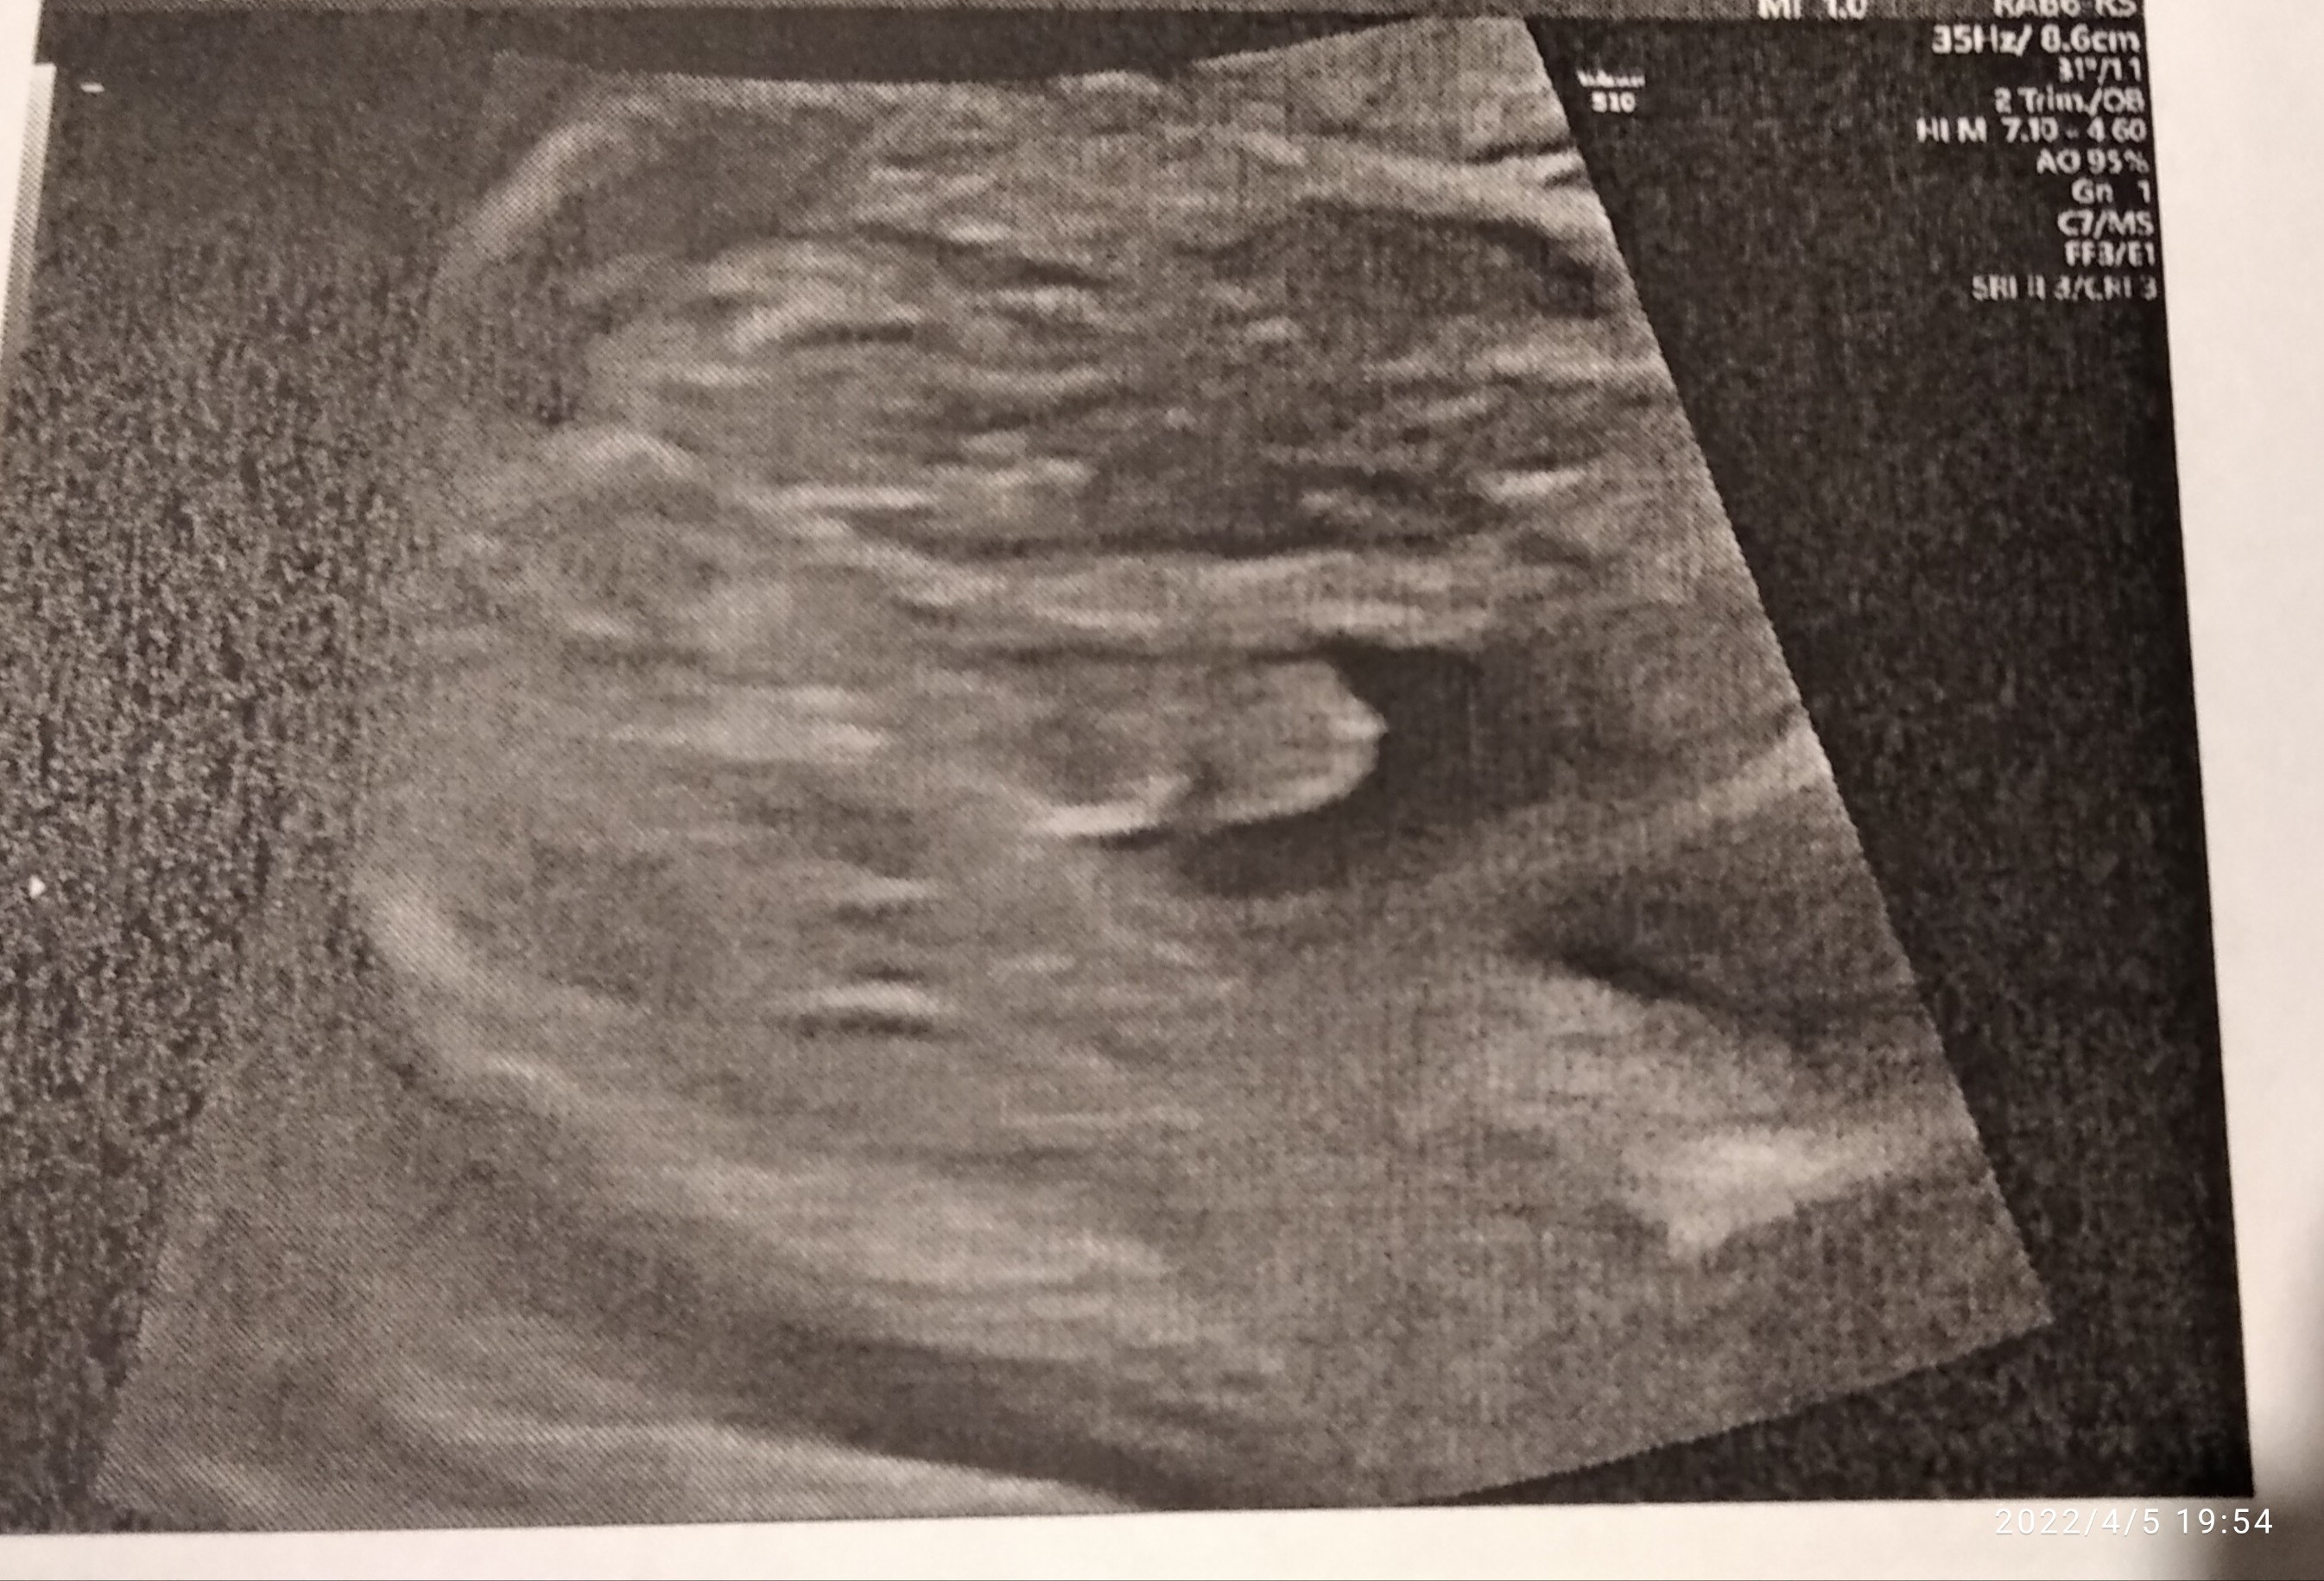

Chłopca już mam 5 lat w czerwcu kończy wiec bardzo bym się ucieszyła jeśli to faktycznie dziewczynka aczkolwiek kto kolwiek to nie jest to i tak już kocham z całegoTo trzymam kciuki żeby było po Twojej myślia wolałabyś chłopca czy dziewczynkę? Ja już jedną córkę mam (8lat) więc z chłopca bardzo się ucieszyłam ☺

No tak, to oczywisteChłopca już mam 5 lat w czerwcu kończy wiec bardzo bym się ucieszyła jeśli to faktycznie dziewczynka aczkolwiek kto kolwiek to nie jest to i tak już kocham z całegoNo ale fajnie by było żeby na 100% wiedzieć jaką wyprawkę szykować jeśli chodzi o ciuszki